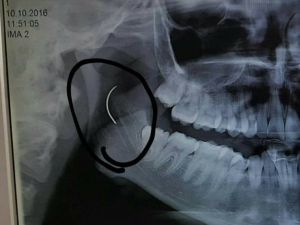

3 yaşında ameliyat oldu, 18 yıl sonra boğazında unutulan iğneden kurtuldu

Boğazında unutulan ameliyat iğnesi 18 yıl sonra alındı